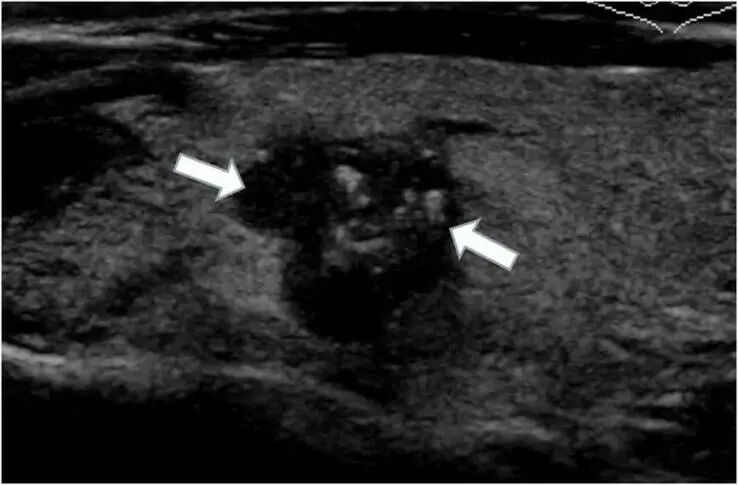

3.彩超檢查:目前甲狀腺檢查的首選項(xiàng)目,不僅可以看到甲狀腺的大小,還可以評(píng)估其血流情況。高分辨超聲可檢出甲狀腺內(nèi)直徑>2mm的微小結(jié)節(jié),清晰地顯示其邊界、形態(tài)及內(nèi)部結(jié)構(gòu)等信息。

5.穿刺活檢:是判斷甲狀腺結(jié)節(jié)良惡性的重要標(biāo)準(zhǔn)。如果超聲甲狀腺結(jié)節(jié)分類較高,或懷疑存在惡性可能,建議進(jìn)一步穿刺活檢,以進(jìn)一步明確診斷。

1.甲狀腺彩超和甲狀腺功能:分別從結(jié)構(gòu)和功能兩方面檢查甲狀腺疾病。甲狀腺彩超不僅操作簡(jiǎn)單、方便,無(wú)創(chuàng),是甲狀腺最常用且首選的影像學(xué)檢查方法。